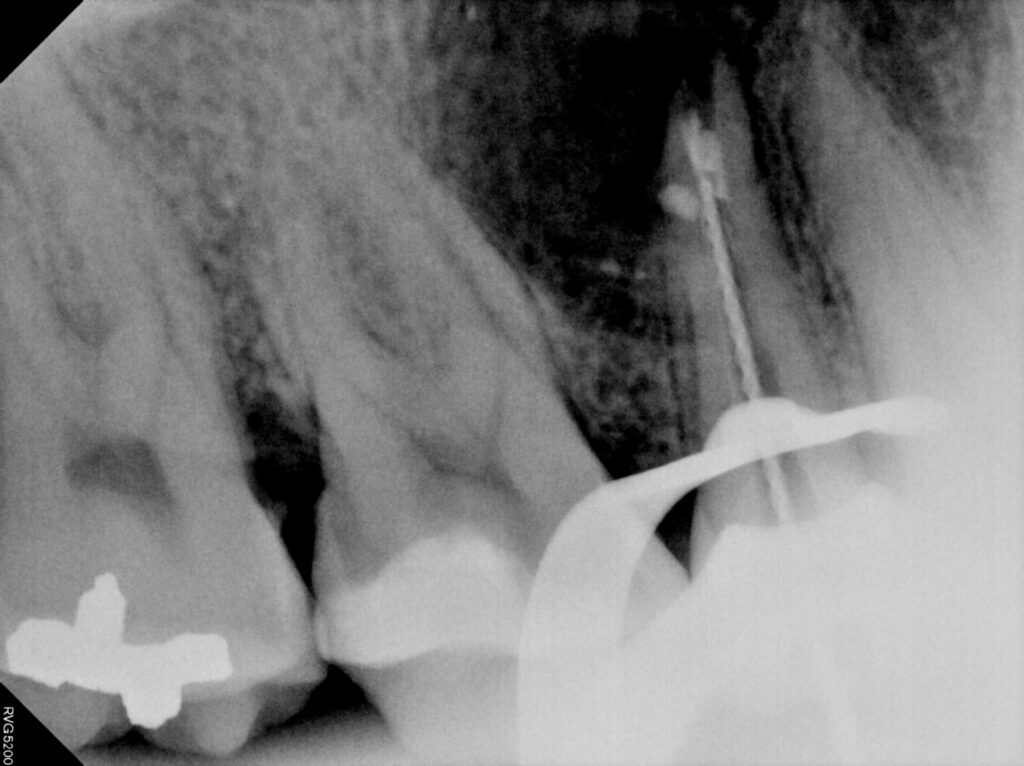

재신경치료의 과정입니다.

치료 시 근관 내 MTA 충전까지

함께 진행하였습니다.

재신경치료는 기존의 근관 충전재를 제거하고

감염된 부위를 다시 소독한 뒤

정밀하게 재충전하는 과정을 거쳐야 하기 때문에

더 정교한 기술과 경험이 요구됩니다.